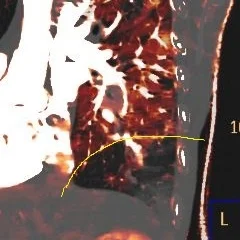

Iodine overlay image on CT Aorta shows the central core of decreased perfusion (outlined in yellow), and a peripheral zone of increased perfusion (outlined in blue). I beleive this is the penumbra.